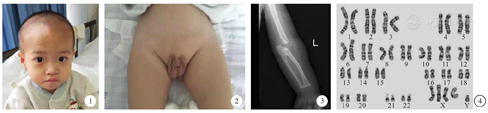

入院查体:体重8.3 kg(<第1百分位),身高76 cm(第3~ 10百分位),神清,精神可,反应一般,可辨亲疏,可逗笑,仅能发单音节,全身未见色素脱失斑,头型对称,头围42.5 cm,眼距稍宽,双侧外斜视,追物欠灵活(图1),听力粗检尚可,颈软,心肺腹部查体无明显阳性体征,阴茎短小,双侧阴囊空虚(图2),脊柱及四肢关节无畸形,四肢肌力Ⅳ级,肌张力低,双侧膝腱反射(++),双巴氏征(-),降落伞反射可引出。可肘支撑,不能直臂支撑,坐位平衡反射可引出,可短暂扶站,不能独站、行。

实验室检查:遗传代谢病筛查未发现特异性改变。心电图提示窦性心律、不完全性右束支传导阻滞。心脏彩超:无明显残余分流。腹部彩超:脾脏囊肿,中极0.8 cm × 0.7 cm。泌尿系彩超、髋关节平片、脑电图等均未见异常。X线检查提示左侧尺桡骨近端骨性融合,肘关节间隙增宽(图3)。脑干听觉诱发电位:两侧V波波形分化差,波幅低平。头颅磁共振平扫:脑实质内未见异常信号,侧脑室饱满。格里菲斯心理发育评估:粗大运动8个月,个人社会7.5个月,听力语言8个月,手眼协调10.5个月,视觉表现7.7个月,各领域百分位数均<1%,发育商50。染色体核型分析为49,XXXXY(图4)。